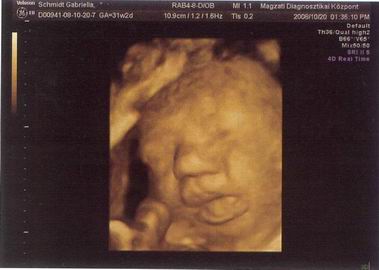

Kicsikristóf a 32. hét elején (vagyis épp egy hete).

BPD: 86 mm

HC: 313 mm

AC: 305 mm

FL: 61 mm

Becsült súly: 2280 gr :shock:

Számított terhesség: 31+2

Biometria alapján: 33+4

itt épp orrba rúgja magát :D

bucifej: